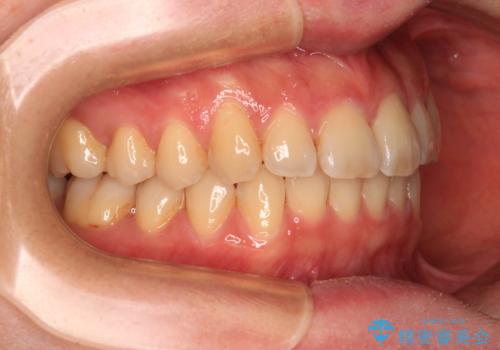

- 上下前歯のデコボコを気にして来院された患者様です。

叢生は軽度で、ワイヤー矯正でもマウスピース矯正でも対応可能な歯列でした。

僅か1年間できれいに歯列を整えることができ、患者様には大変満足していただきました。